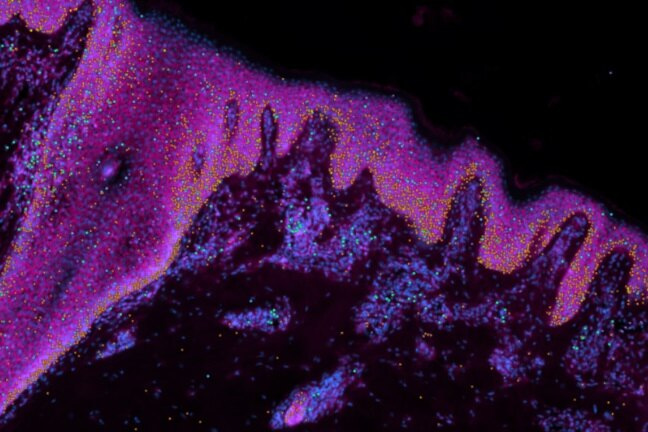

Исследователи из Кембриджского института стволовых клеток впервые создали подробный атлас кожи человека до рождения, чтобы понять, как формируется кожа и что происходит при ее заболеваниях. Ученые считают, что исследование поможет выработать клинические методы, позволяющие залечивать раны без шрамов и выращивать волосяные фолликулы, что может помочь при облысении.

Эти знания могут быть использованы для создания новых волосяных фолликулов в регенеративной медицине и при пересадке кожи пострадавшим от ожогов. В исследовании, опубликованном в журнале Nature, команда создала «мини-орган» кожи, обладающий способностью выращивать волосы.

Используя органоид, ученые показали, что иммунные клетки играют важную роль в восстановлении кожи без рубцов. Это может найти клиническое применение для предотвращения образования рубцов после операций или заживления ран без рубцов.

В рамках проекта «Атлас клеток человека», в котором отображаются все типы клеток человеческого организма, исследователи представили молекулярный «рецепт» для создания кожи и новую органоидную модель для изучения врожденных кожных заболеваний.